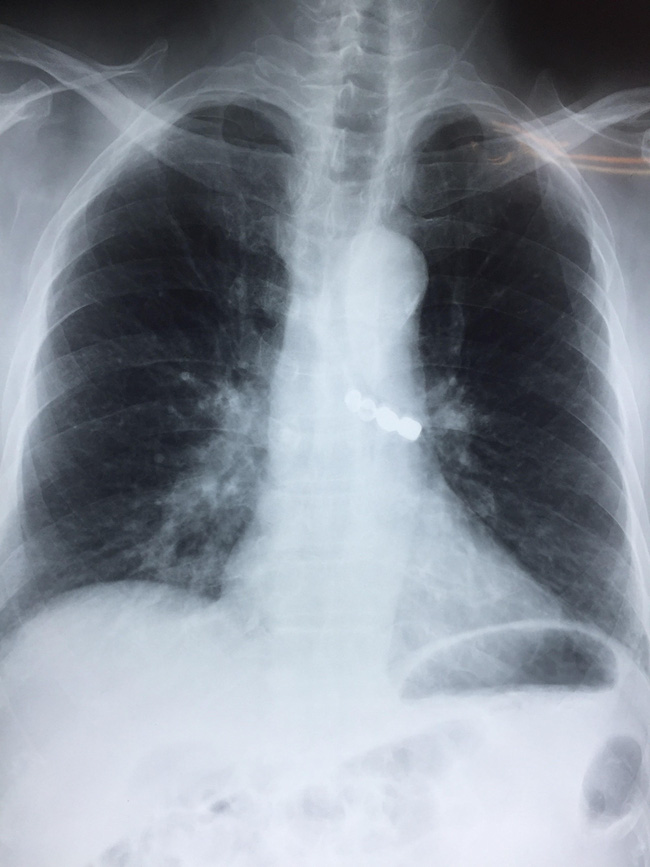

Dị vật nằm sâu trong phế quản khiến bệnh nhân khó thở, đe doạ tính mạng - Ảnh: Bác sĩ cung cấp

Trước đó, cụ ông này có đi làm răng giả nhưng không may bị sự cố rơi mất răng giả. Người bệnh đã được nội soi dạ dày tại Bệnh viện tỉnh Thái Bình để tìm dị vật nhưng không thấy; được chụp phim X-quang phổi và phát hiện ra dị vật trong đường thở. Do vượt quá khả năng can thiệp nên cụ ông 90 tuổi được lên tuyến trên.